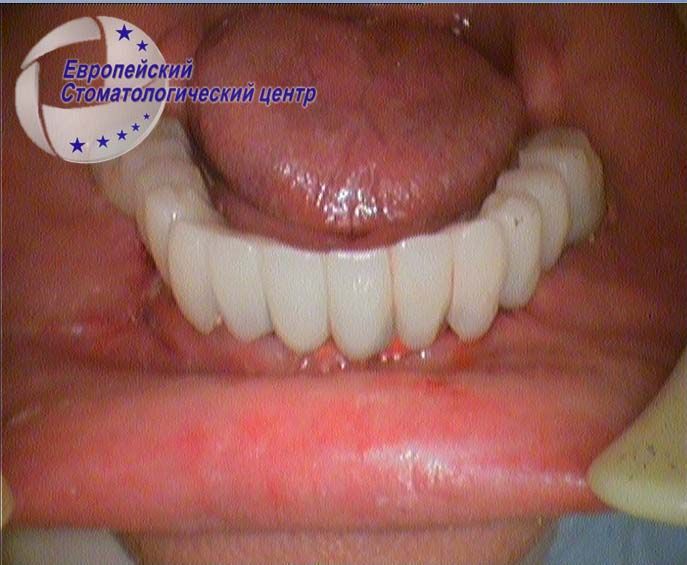

| ![]() | Рис.4 — Клиническая картина полости рта на второй день после проведения имплантации |

| ![]() | Рис.4.1 — Немедленное протезирование на третий день после операции временными несъемными металлопластиковыми конструкциями. |

Проведенный хирургический этап дентальной имплантации предусматривал немедленную функциональную нагрузку временным несъемным комбинированным протезом с пластмассовым покрытием, которым пациентка имела возможность пользоваться уже через 3 дня после проведенного хирургического вмешательства. Достаточное количество имплантатов значительной длины, практическое соответствие осей протеза и имплантатов практически исключает возникновение таких рисков, как уменьшение надежности ретенции протеза, переломов имплантата и неадекватной функциональной нагрузки на них.

Послеоперационный период протекал без осложнений, состояние слизистой оболочки вокруг имплантатов – удовлетворительное. Каких-либо жалоб пациентка не предъявляла.

Клинически у пациентки определяли неподвижность имплантатов, отсутствие негативных проявлений при перкуссии, отсутствие болевого инфекционного синдрома вокруг имплантатов и отсутствие явлений парестезии.